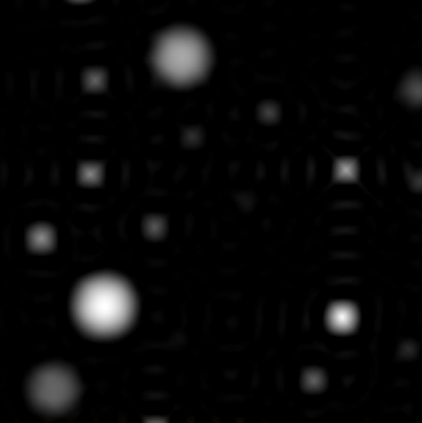

Implicit neural representations (INRs) have emerged as a powerful tool for solving inverse problems in computer vision and computational imaging. INRs represent images as continuous domain functions realized by a neural network taking spatial coordinates as inputs. However, unlike traditional pixel representations, little is known about the sample complexity of estimating images using INRs in the context of linear inverse problems. Towards this end, we study the sampling requirements for recovery of a continuous domain image from its low-pass Fourier coefficients by fitting a single hidden-layer INR with ReLU activation and a Fourier features layer using a generalized form of weight decay regularization. Our key insight is to relate minimizers of this non-convex parameter space optimization problem to minimizers of a convex penalty defined over an infinite-dimensional space of measures. We identify a sufficient number of samples for which an image realized by a width-1 INR is exactly recoverable by solving the INR training problem, and give a conjecture for the general width-$W$ case. To validate our theory, we empirically assess the probability of achieving exact recovery of images realized by low-width single hidden-layer INRs, and illustrate the performance of INR on super-resolution recovery of more realistic continuous domain phantom images.